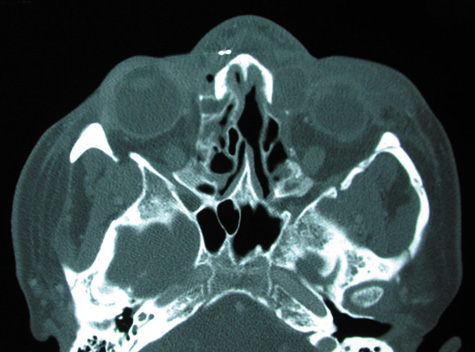

CT shows sinusitis with or without bone destruction and is indistinguishable from other causes of orbital cellulitis.128 MRI may show carotid narrowing, occlusion, and absent flow in the superior ophthalmic vein (Fig. 24).72

Fig. 24. Mucormycosis. A. A 72-year-old patient with acute myelogenous leukemia and invasive fungal sinusitis presented with orbital cellulitis. B. Involvement of hard palate with eschar. C. Fungi in the posterior ciliary artery.